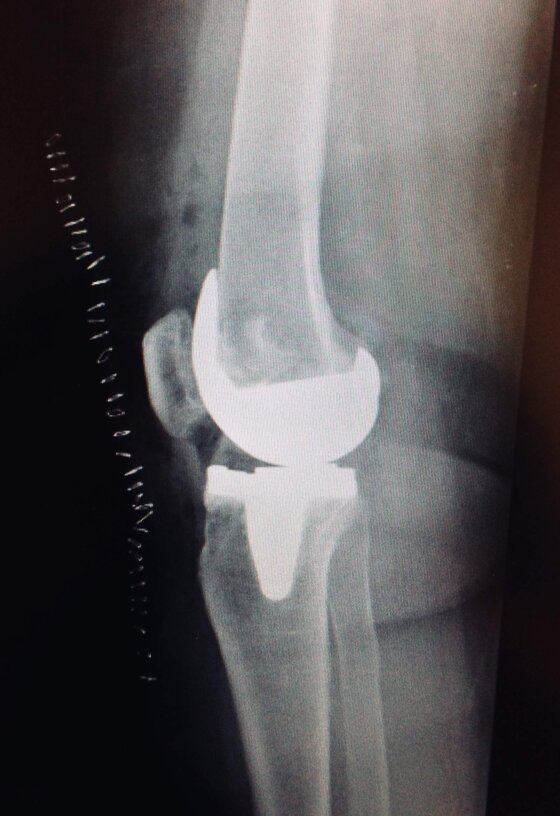

A sinistra radiografie pre-operatorie il AP e LL che evidenziano una grave gonartrosi diffusa con presenza di osteofiti periarticolari e deformità associata (ginocchio varo).

A destra radiografia post-operatoria in AP e LL di intervento chirurgico di artroprotesi di ginocchio cementata, unico trattamento possibile con pz che presentava dolore continuo e zoppia. Ho utilizzato una protesi con risparmio del legamento crociato posteriore (CR) chiamata Persona proprio perché altamente anatomica, cioè molto rispettosa dell’anatomia del ginocchio del singolo paziente. La paziente presentava un sovrappeso per cui ho optato per una componente protesica tibiale con un fittone più lungo proprio per avere più resistenza